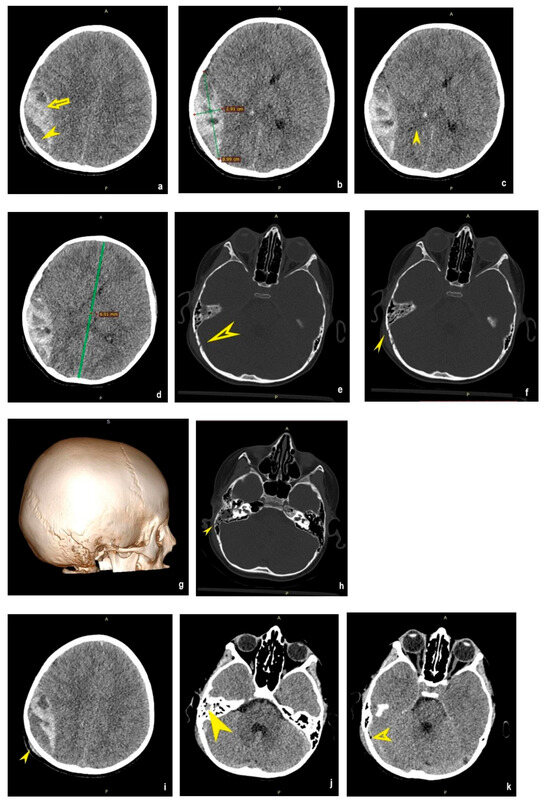

2.2. Second Case Report